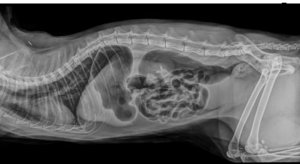

Hier Die Röntgenbilder das schwarze das zu sehen ist- ist das Augegaste.

53508ECC-0DD1-43B2-96DC-80E0F4C897AF.jpeg38B1B5B7-ACAB-402B-8249-9D48217B2176.jpeg

Emily war ganz aufgegast sie hatten Ultraschall gemacht Röntgenbilder hatte der Tierarzt Notdienst bei dem ich war der TK weitergeleitet.

Nach Medikamentengabe ist die Aufgasung zurückgegangen sodass man einen Fremdkörper ausschliessen kann.

Das Gas war aber noch im Verdauungstrakt, sodass man nicht alles mit dem Ultraschall sehen konnte.